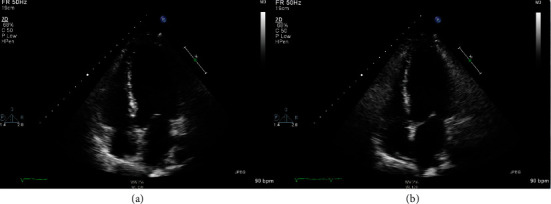

West Nile Virus (WNV) myocarditis is nearly fatal, according to the current medical literature. We report a previously healthy 37-year-old Caucasian male who presented to our facility with two days of progressive lower extremity weakness, fever, edema, and shortness of breath found to have left ventricular global hypokinesis with an ejection fraction of less than 25%, consistent with acute viral myocarditis. He also has concomitant WNV meningoencephalitis due to his altered mentation. He was found to have a positive serum WNV IgM suggestive of a diagnosis of WNV myocarditis. He was intubated and was placed on vasoactive pressors for supportive care due to evidence of mixed cardiogenic and septic shock. After two weeks of hemodynamic support, we discovered a near-complete cardiac recovery, as shown on a repeat transthoracic echocardiography (TTE) and a normalized mean arterial blood pressure. This is a unique case report because near fatality is often associated with WNV myocarditis secondary to tachyarrhythmia, and there are currently no documented cases that are suggestive of cardiac recovery from the current literature.

根据目前的医学文献,西尼罗河病毒(WNV)心肌炎几乎是致命的。我们报告一名先前健康的37岁白人男性患者,他以进行性下肢无力、发热、水肿和呼吸短促的症状向我们就诊,发现左心室整体运动不足,射血分数小于25%,符合急性病毒性心肌炎。由于他的精神状态改变,他还伴有西尼罗河病毒脑膜脑炎。血清WNV IgM阳性提示WNV心肌炎的诊断。由于有心源性和感染性休克混合的证据,他被插管并使用血管活性加压药物进行支持治疗。经过两周的血流动力学支持,我们发现心脏几乎完全恢复,如重复经胸超声心动图(TTE)和标准化平均动脉血压所示。这是一个独特的病例报告,因为继发于心律失常的西尼罗河病毒心肌炎通常与接近死亡有关,目前尚无文献记载的病例提示心脏恢复。